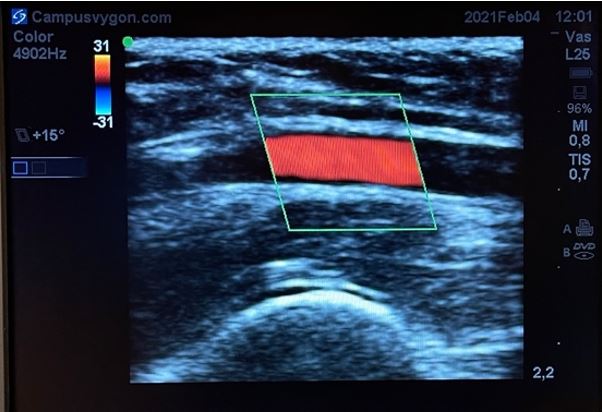

Cuando se estudia un vaso longitudinalmente con modo doppler color, puede ser útil emplear la opción de angulación de la caja de color, de tal manera que ahora los ultrasonidos se emitan angulados desde la sonda.

Esto facilita la identificación del vaso, sin tener que bascular la sonda en la piel del paciente. Teniendo en cuenta la posición de la muesca del transductor respecto a la pantalla y la angulación del ROI, podremos discernir la dirección del flujo estudiado mediante la misma regla: el flujo que se acerca al transductor será de color rojo y el que se aleja de color azúl.